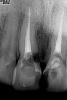

x3m Опубликовано 2 апреля, 2013 Поделиться Опубликовано 2 апреля, 2013 (изменено) Красиво))Олег, шаблон был? если да - какой?какие габариты имплантата?какой торк при установке?чем-то обсыпал? зы. удалял целиком или фрагментами? (зуб после удаления, похоже, склеен?) ззы. у меня похожий кейс планируется (недавний снимок):в прошлом году было реэндо, планировал ВКВ ДЦ + пресс...сейчас присматриваюсь - уже тогда, похоже, была небольшая тень внешней резорбции... но за полгода (отчего бы?) прогресс очень налицо сделали КоТэ, локализация - мезиально-небная. Изменено 2 апреля, 2013 пользователем x3m Ссылка на комментарий

Bier Опубликовано 2 апреля, 2013 Автор Поделиться Опубликовано 2 апреля, 2013 Красиво))Олег, шаблон был? если да - какой?какие габариты имплантата?какой торк при установке?чем-то обсыпал? зы. удалял целиком или фрагментами? (зуб после удаления, похоже, склеен?) ззы. у меня похожий кейс планируется (недавний снимок):в прошлом году было реэндо, планировал ВКВ ДЦ + пресс...сейчас присматриваюсь - уже тогда, похоже, была небольшая тень внешней резорбции... но за полгода (отчего бы?) прогресс очень налицо сделали КоТэ, локализация - мезиально-небная. Без шаблона. Имплантат hi-tec как нобель актив 4,3*13Торк около 50Добавлял остеобиол путти (между имплантатом и костью) + вестибулярно сст Тут резорбция внутренняя. Ссылка на комментарий

Bier Опубликовано 2 апреля, 2013 Автор Поделиться Опубликовано 2 апреля, 2013 Делали внутриканальное отбеливание ? очень похоже на резорбцию после вн отбела Никакого внутриканального отбеливания не было. Зуб был интактный. Ссылка на комментарий